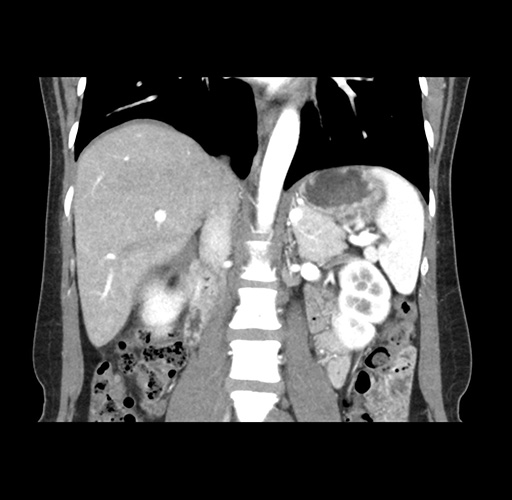

Imaging Analysis

Look through the patient's CT scan to identify any areas of concern for the necessary procedure.

Based on your CT findings, which issue(s) would give reason for "planned slowing down moment(s)" in this case?